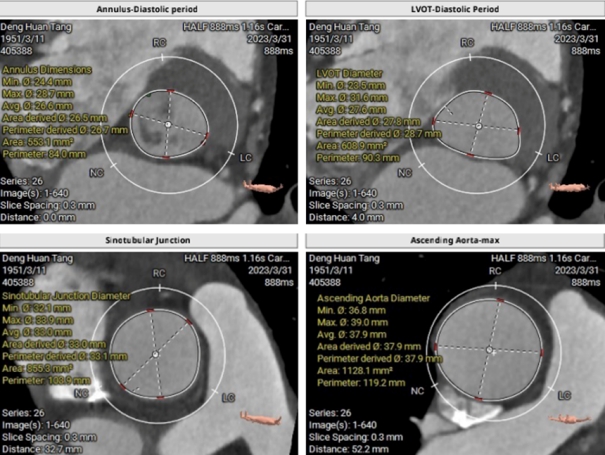

经心脏中心卢才义主任、李龙虎主任团队分析研判:此例患者结合临床明显瓣膜病症状以及在术前心室造影综合评估得出,此例患者为Type0二叶式重度主动脉瓣返流病人,瓣环周长84mm,LVOT周长90.3 mm,瓦式窦长径40.9mm,短径24.4mm,STJ 均径33.1mm,升主动脉均径35.2mm,左冠高度17.5mm,右冠高度14.4mm,下肢入路血管条件可。但CT造影提示主动脉瓣叶脱垂,流出道呈喇叭口状,且窦内钙化较轻缺乏有力锚定,考虑到植入后的人工瓣膜有一定的压缩比,锚定条件可,但不可过深植入,所以本次瓣膜的植入深度和瓣膜的锚定位置情况是本次手术的重要关键点。